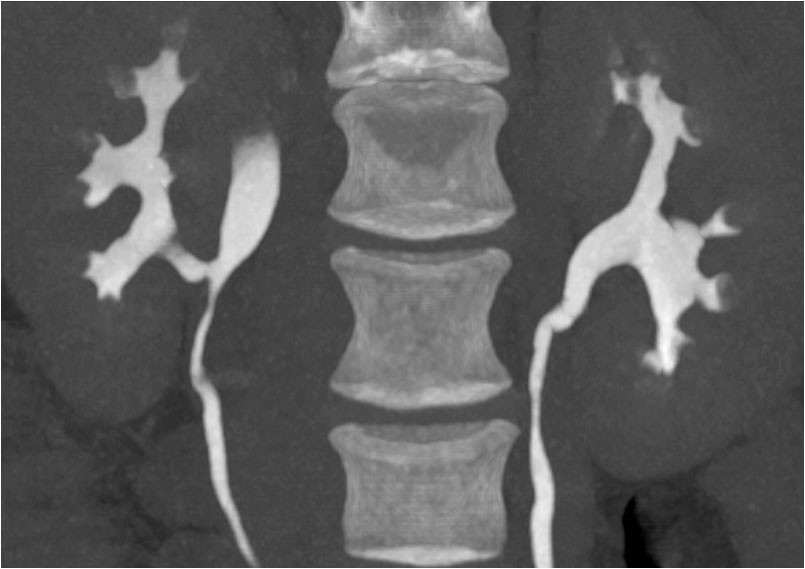

CT av urinveier ble utført, men det var ikke mulig å gi noen konklusjon med hensyn til ektopisk munnende ureter. Det ble derfor utført MR av urinveiene. Det forelå dobbeltanlegg på høyre side med et lite øvre anlegg og et dilatert ureter (fig 1). Ureter forløp dilatert mellom urinblære og vagina og munnet ut ektopisk nær urethras utmunning (fig 2).

For å identifisere dobbeltanlegg og ektopisk munnende ureter på CT forutsettes tilstrekkelig funksjon og kontrastutskilling fra det øvre anlegget, noe som ikke var tilfellet for denne pasienten. Ultralyd kan identifisere dilatert, ektopisk ureter, men det kan være vanskelig og krever som regel spesiell oppmerksomhet. Vår pasient var henvist med spørsmål om kolelitiasis og pyelonefritt, og det ble ved rutinemessig vurdering av urinveiene ikke oppdaget patologi. Høyoppløselige væskesensitive MR-sekvenser i volumopptak gir gode forutsetninger for å identifisere ureter og følge ureters forløp. I det lille bekken er MR bedre egnet enn CT, men mer tidkrevende. Det ble utført dedikerte høyoppløselighetsserier i bekkenet supplert med mindre detaljrike sekvenser over øvre urinveier. Det ble ikke benyttet kontrastmiddel under MR-undersøkelsen. Barnelegene bruker MR som primær modalitet ved mistanke om ureteral ektopi.

Ved postoperativ tremånederskontroll var urinlekkasjen borte. Hun kunne merke litt mukøst sekret i trusen om morgenen. Man antok at dette kunne være fra gjenværende distale ende av ektopisk ureter og vurderte at symptomene ikke krevde ytterligere tiltak. Hun opplevde noe ømhet i høyre flanke, som ble vurdert som en postoperativ muskulær plage. Likevel ble det rekvirert CT urografi for å vurdere postoperativ status. Undersøkelsen viste, som ventet, ingen kontrast i ureter fra øvre anlegg, men normal utskilling via nedre ureter til urinblæren. Det var ingen tegn til hydronefrose (fig 6).